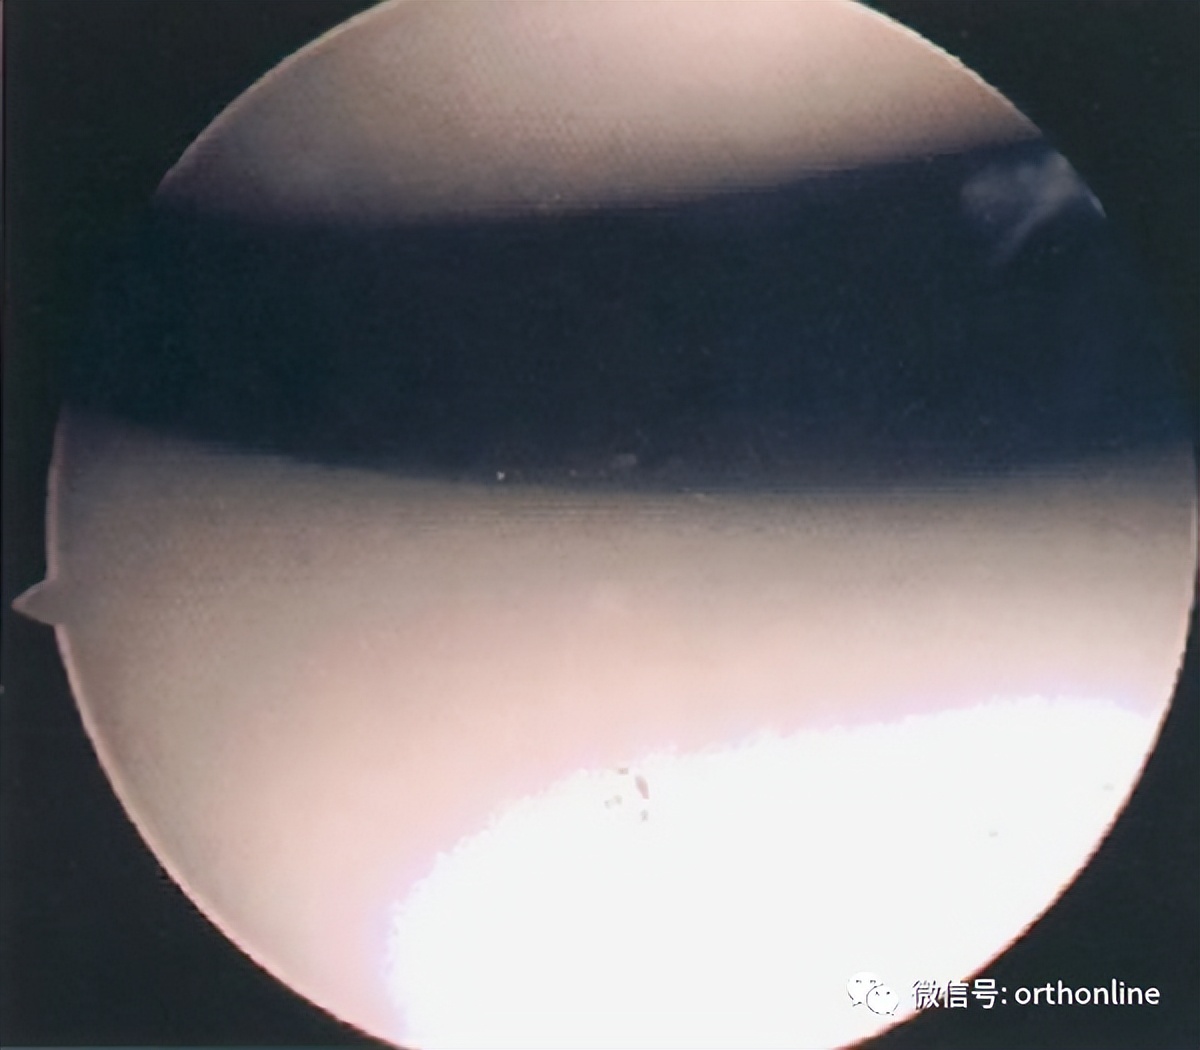

关节镜下髌骨软化症0级表现